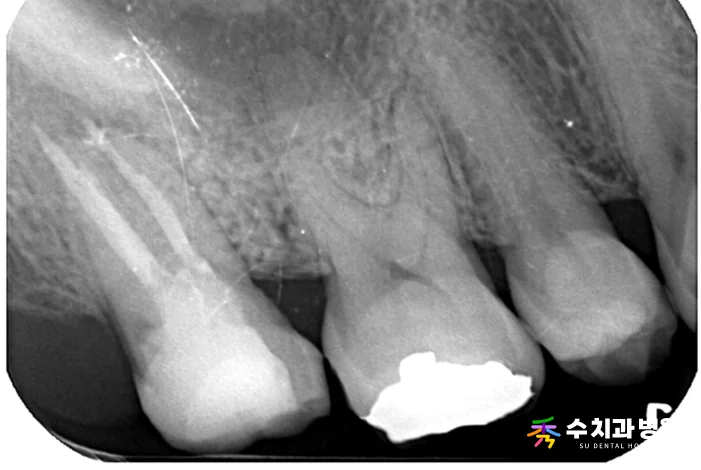

[📸 치료 전 엑스레이] (촬영일: 2023년 8월)

방사선 및 임상 검사를 꼼꼼히 진행한 결과,

과거에 신경치료를 마쳤던 치아의 뿌리 끝 부위에

명확한 염증 소견이 관찰되었습니다.

기존에 씌워둔 보철물을 조심스럽게 제거해 보니,

보철물 경계 틈으로 세균이 유입되면서

2차 충치가 깊게 진행된 상태였습니다.